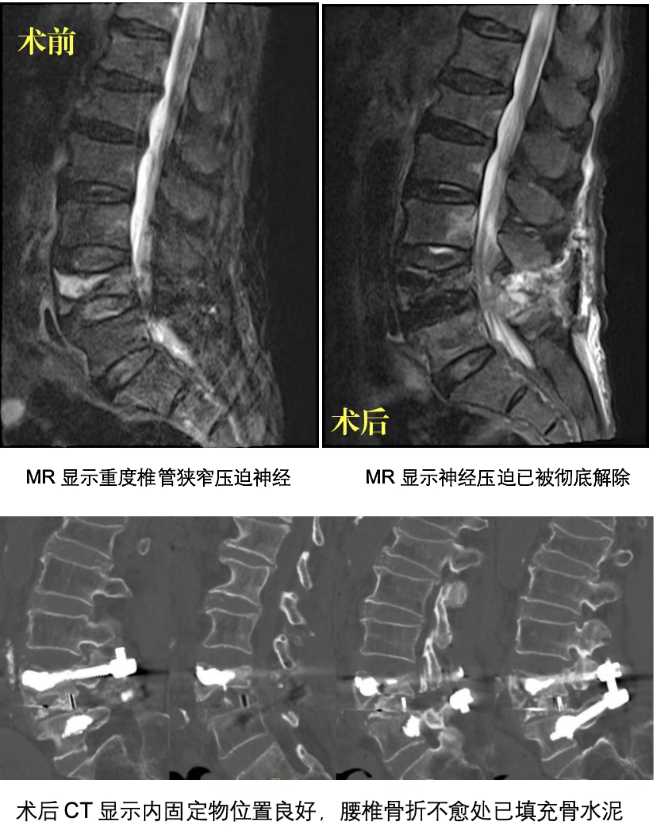

接诊的陈晓峰主任医师介绍道:“患者是腰椎骨折不愈并发继发性椎管狭窄,疼痛评分达8分,因痛感无法入睡,已出现肌肉力量下降等神经损伤进展迹象,保守治疗无效,必须通过手术才能尝试解除压迫,但手术风险又超乎寻常地高。” 98岁的高龄意味着身体机能已经接近极限,肺气肿又增加了麻醉与术后呼吸管理的难度,低蛋白血症与营养不良还会直接影响伤口愈合与植骨融合,骨质疏松更是给椎弓根钉固定带来巨大挑战,螺钉在疏松的骨骼中极易松动,可能导致手术功亏一篑。

“患者肺功能较差,全麻需采用保护性通气策略。”“术前先通过肠内营养补充,将白蛋白指标提升至安全范围。”“椎弓根钉固定时需精准定位,最大限度减少骨量损失。”…… 经过反复推演风险预案,专家们最终明确手术指征,排除禁忌症,为患者量身定制了 “后路腰椎椎管狭窄椎板切除 + 椎弓根钉内固定 + 植骨融合术” 方案,并制定了详尽的围手术期管理计划。

手术由陈晓峰主任医师主刀,麻醉科、重症医学科团队全程保驾护航。术中,陈晓峰主任团队精准定位椎弓根钉置入点,仅用不到两小时就完成了椎管减压、螺钉固定与植骨融合等关键步骤,术中出血少,远低于常规手术水平。当麻醉苏醒后,禤爷爷第一句话便说:“腿不疼了,舒服多了!”